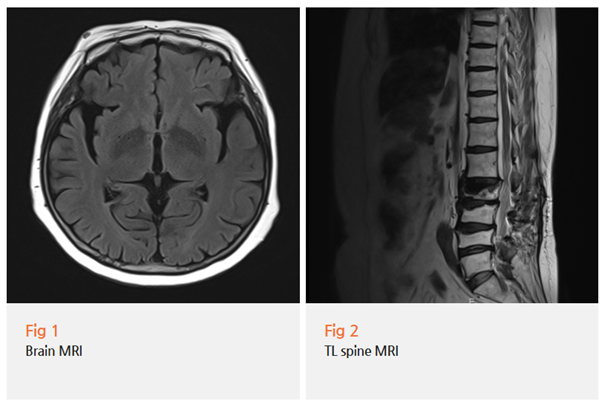

환자분께서 말씀하시길, 이미 다른 병원 두 곳에서

뇌 MRI, MRA 검사까지 다 했대요.

그런데 결과는 "별 이상 없다"였고,

손떨림 약을 처방받았지만 효과가 거의 없었다고 하셨죠.

이게 참 안타까운 부분이에요.

MRI에서 이상이 안 나온다고 해서 문제가 없는 건 아니거든요.

특히 파킨슨병 초기에는 MRI상 뚜렷한 변화가 잘 안 보입니다.

다시 뇌 MRI를 찍었고, 신경학적 검진을 더 자세히 진행했어요.

그리고 결과적으로 파킨슨병 진단을 내릴 수 있었습니다.